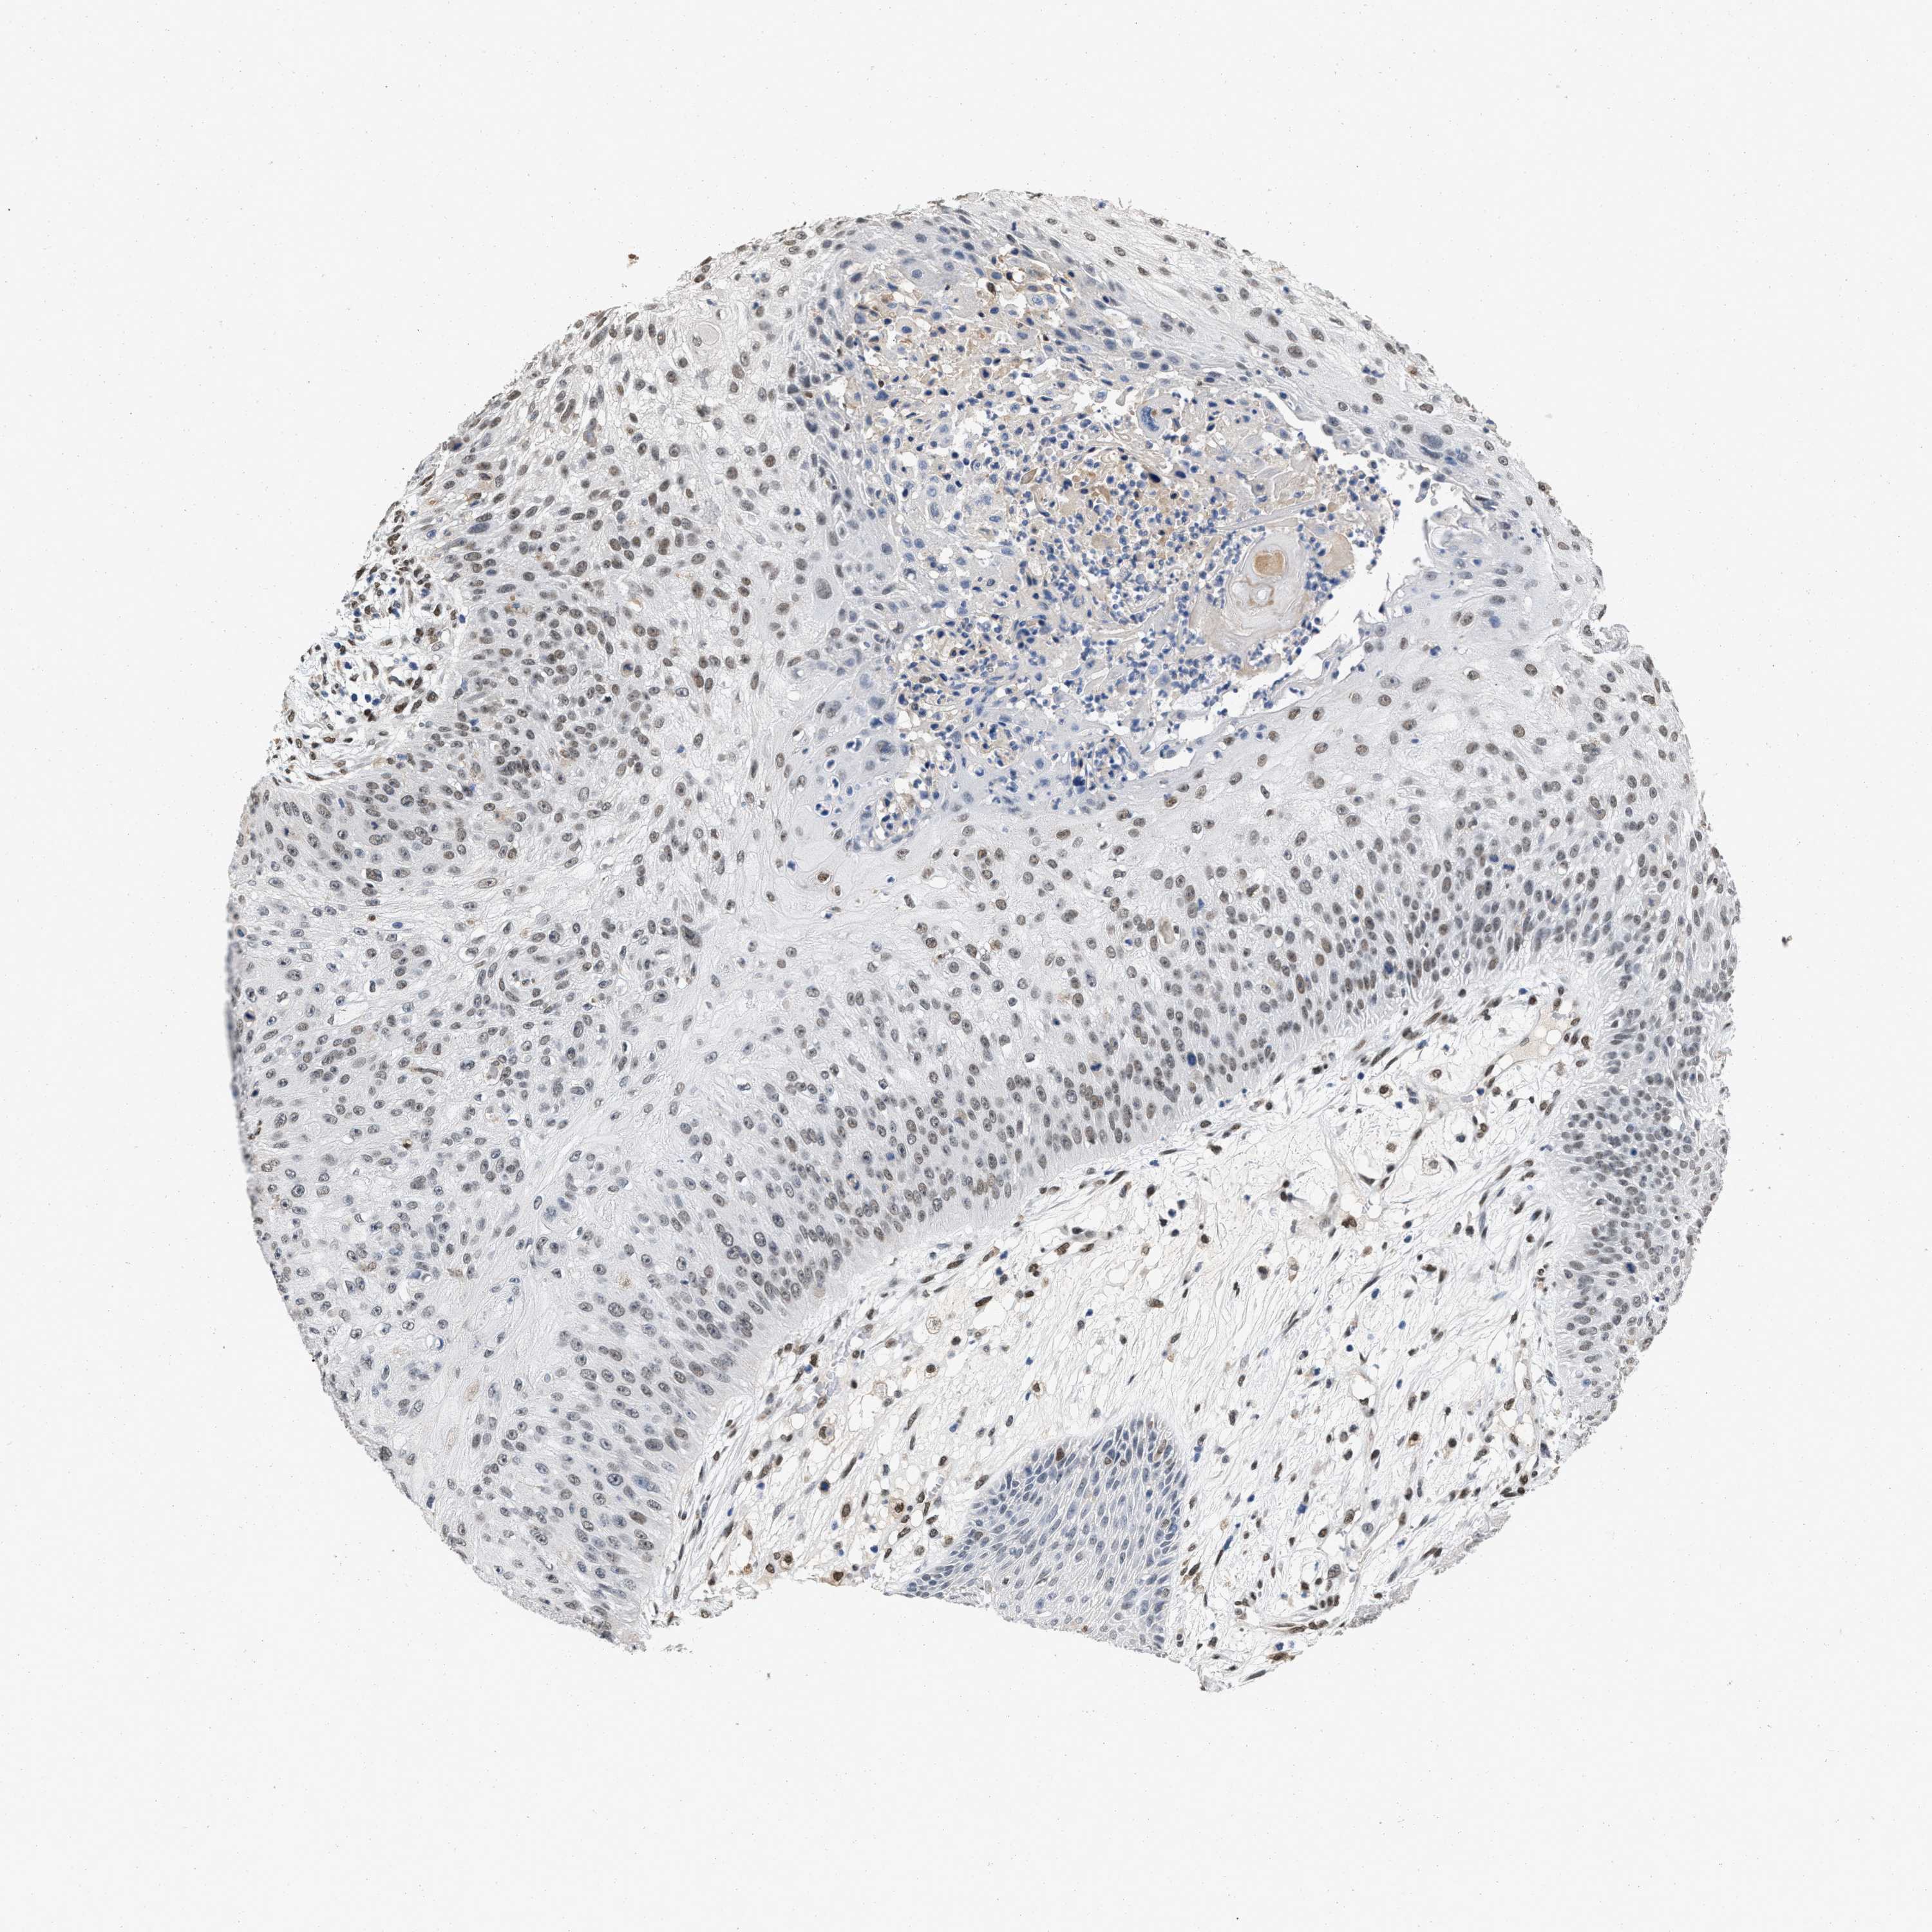

SKIN CANCER - Protein expressioni

A mouse-over function shows sample information and annotation data. Click on an image to view it in a full screen mode. Samples can be filtered based on level of antibody staining by selecting one or several of the following categories: high, medium, low and not detected. The assay and annotation is described here.

Each image is clickable and will lead to virtual microscopy that enables deeper exploration of all samples and also displays staining intensity scores, fraction scores and subcellular localization as well as patient and tissue information for each sample.

Antibody HPA019123

Antibody CAB022602

Staining

High

Medium

Low

Not detected

Intensity

Strong

Moderate

Weak

Negative

Quantity

>75%

75%-25%

<25%

None

Location

Nuclear

Cytoplasmic/membranous

Cytoplasmic/membranous,nuclear

Squamous cell carcinoma in situ, NOS

Squamous cell carcinoma, NOS

Squamous cell carcinoma, metastatic, NOS

Basal cell carcinoma